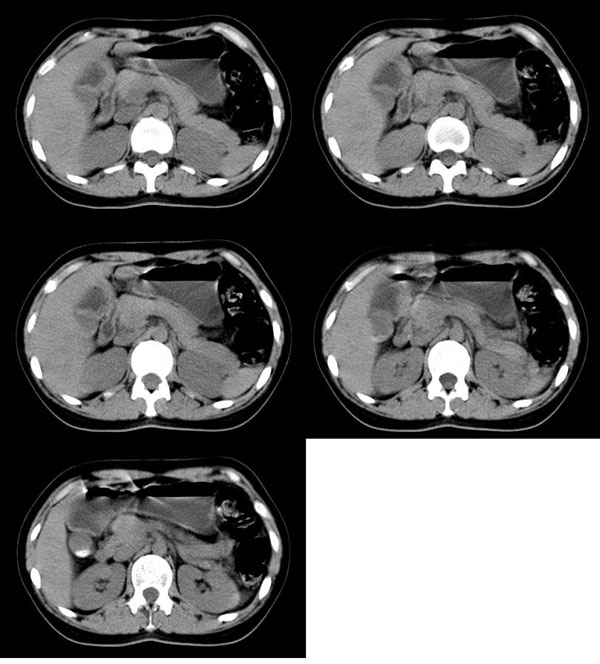

以下是引用guzhongliangddd在2006-11-9 17:55:00的发言:[br]请重点讨论图中箭头所示{脾门部,我首先考虑的是1:血管结构2:胰尾组织??)[br][br][本贴已被 guzhongliangddd 于 2006-11-9 18:01:50 修改过]

以下是引用无泪之城在2006-11-9 20:01:00的发言:[br]考虑副脾,建议增强,请把增强片传上来

以下是引用西北偏北在2006-11-9 20:15:00的发言:[br]箭头所指结构边缘不光整,不支持副脾,考虑胰尾容积层面或血管,做个增强吧.